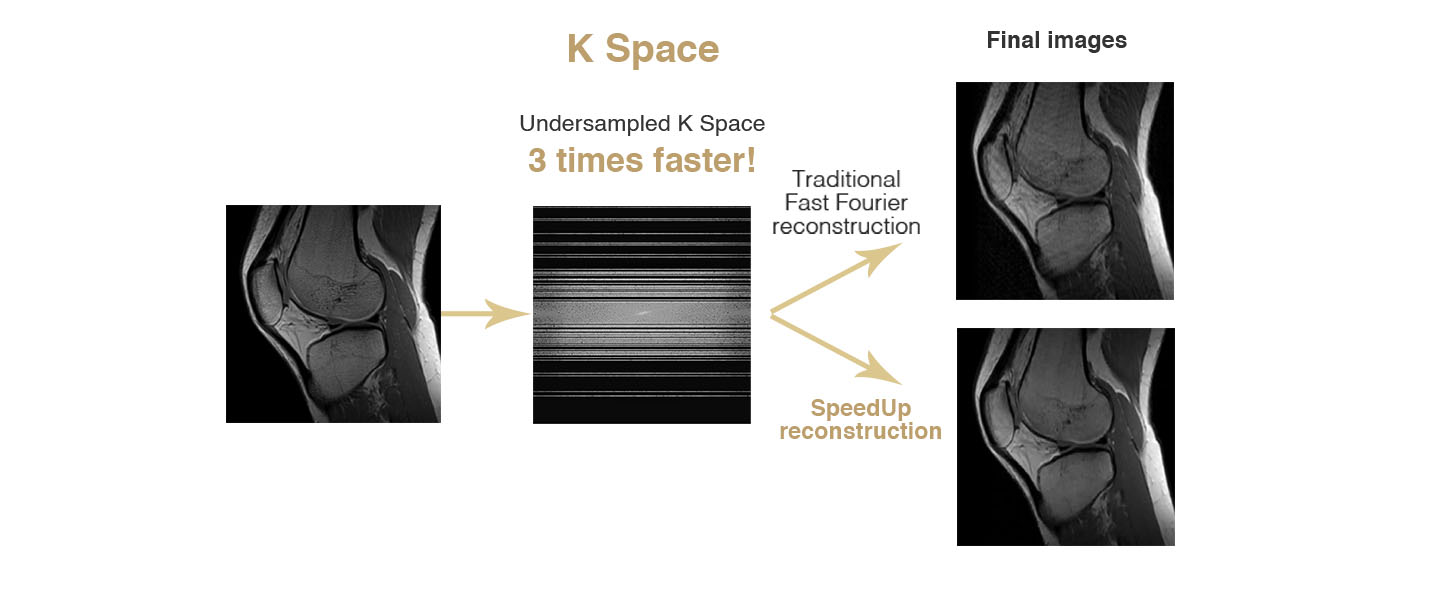

SpeedUp: How does it work and what does it do?

Faster exams:

SpeedUp allows sensible reduction of the scan time through a in-choerent sparse sampling of the K Space.Reduces artifacts and noise:

SpeedUp technique through an iterative nonlinear regression algorithm permits to reduce image artifacts and background noise improving overall image quality.